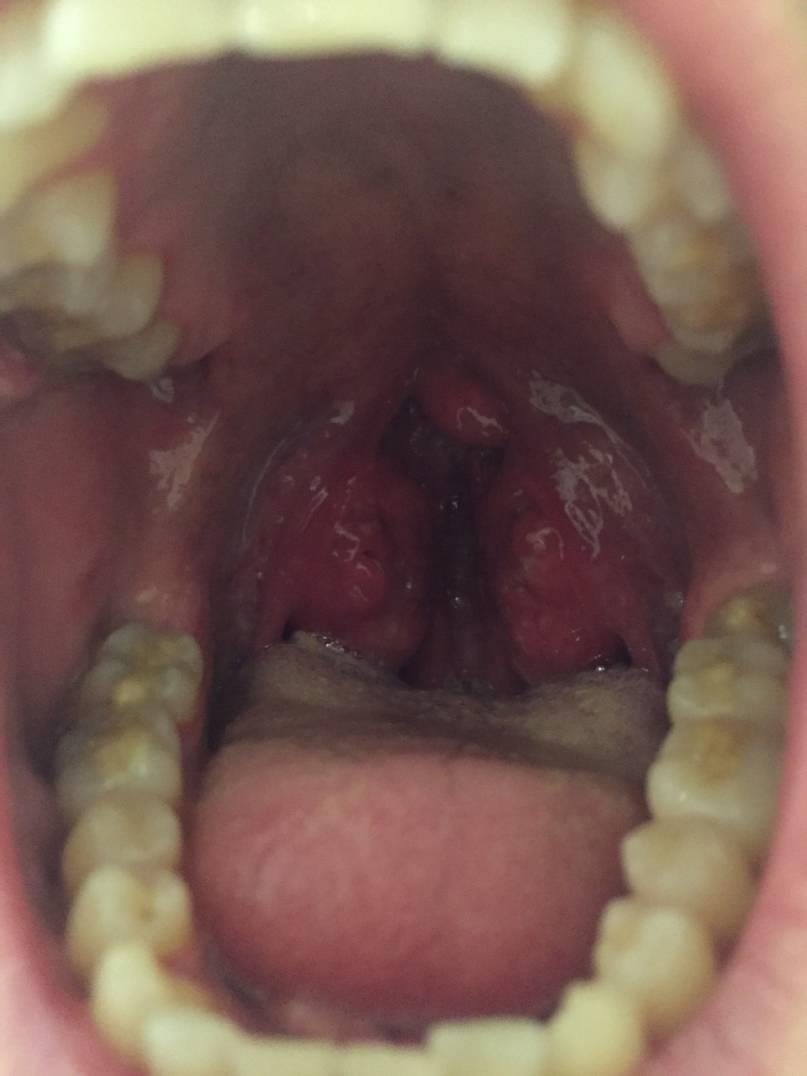

Во время визуального осмотра зева пациента определяется гиперемия (покраснение) гланд и стенок горла.

На фото ангина Симановского

При непосредственном осмотре области миндалин визуализируется пленка беловато-желтовато-серого цвета. По внешнему виду она напоминает пятно от стеариновой свечки округлой формы. Пленка мягкая (по консистенции), окружена воспалительным (красным, отечным) ободком по краю и легко снимается ватным тампоном, после чего на его месте остается изъязвленная поверхность желтоватого цвета с ровными четкими контурами, которая кровоточит.

Для пораженной миндалины характерно увеличение в размерах. Она покрывается серовато — желтым налетом с дурным запахом. Его легко можно убрать медицинским шпателем. Симптомы гнойно воспалительного поражения проходят за 2 недели.